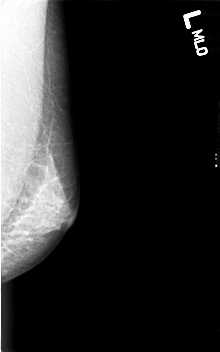

B_3003_1.LEFT_MLO

LEFT_MLO LINES 4568 PIXELS_PER_LINE 2848 BITS_PER_PIXEL 12 RESOLUTION 50 NON_OVERLAY